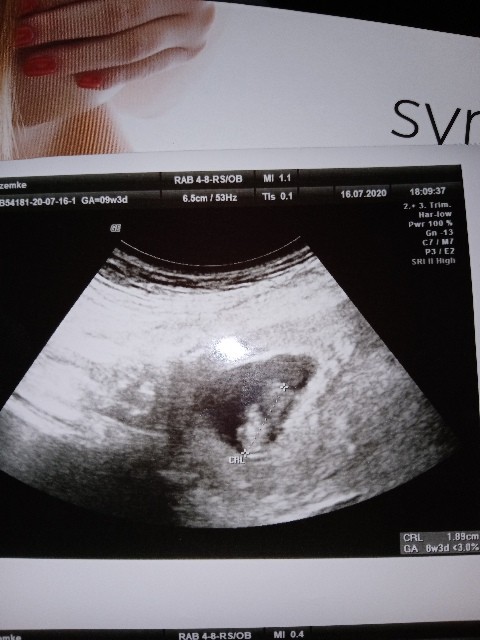

Ja tak miałam, okazało się że ciąża jest 2 tyg młodsza niż wychodzi z ostatniej @, więc wszystko jest możliwe.Może miałaś później owulację i stąd jest mniejsze bądź dobrej myśli.